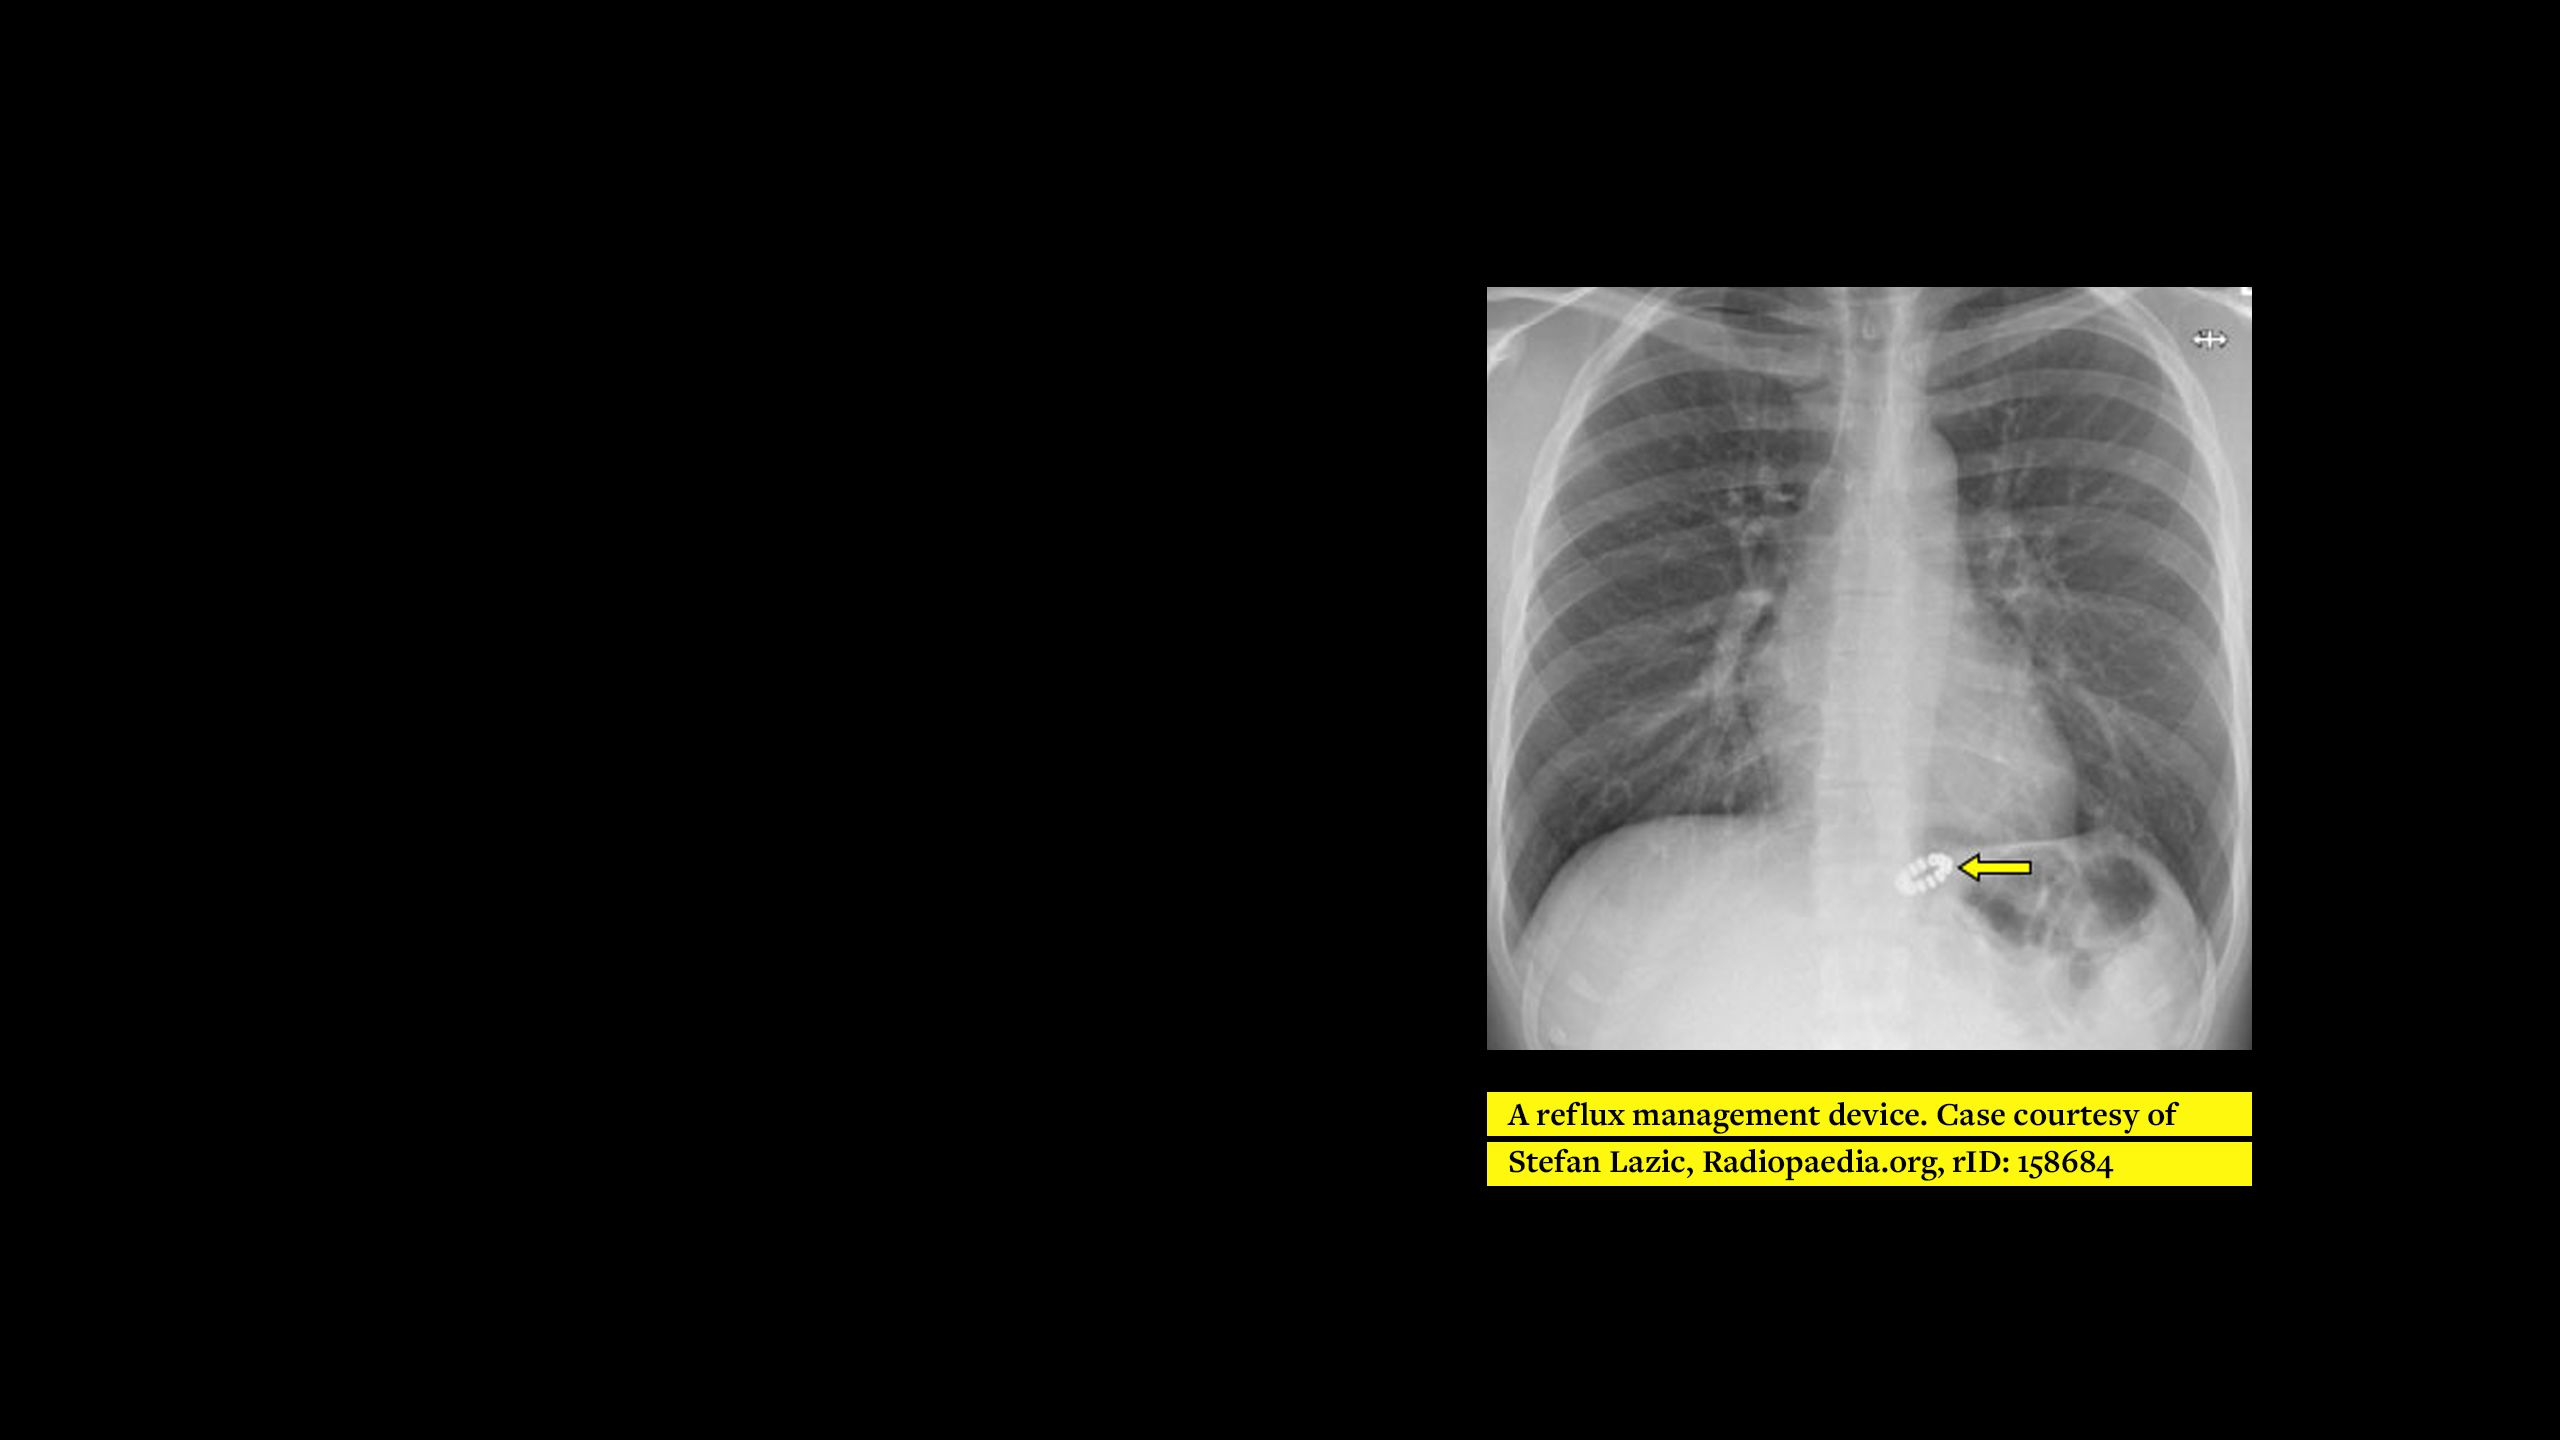

This e-learning programme is designed to raise awareness of different medical devices and to allow better utilisation of X-rays to confidently find and name them. While open to everyone, the training is specifically designed for Diagnostic and Therapeutic Radiographers for MRI safety screening. It is meant to highlight implants that may be specific to certain specialities; for example, cardiac or neuro, and therefore difficult to identify in departments outside of those specialities. Additionally, implants may be commonly known, but not easily recognisable on imaging. It also hopes to appeal to radiographers with different levels of experience and knowledge.

The training describes the appearance and most common locations of each implant and tries to explain various ways of differentiating between implants where possible. The reason for implantation is also stated to further assist identification and allow correlations to be made with the patient’s given information and medical records.

The ‘chest’ module represents the first of four to focus on implanted medical devices. The next modules in the series (abdomen/pelvis, head/neck and extremities) are under development and are due to be released soon.